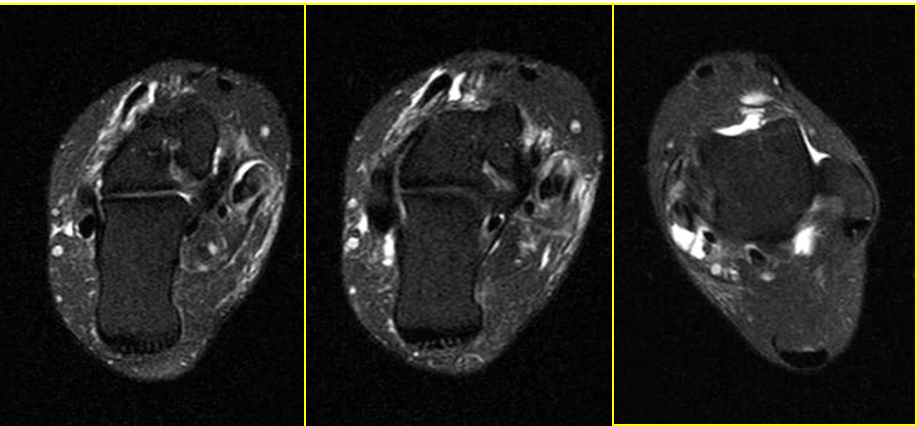

胫前、胫后肌腱撕裂

MR表现:

• 胫骨前肌腱较少发生撕裂,一旦发生,多为全肌腱损伤

• 胫骨后肌腱出现横截撕裂或纵行撕裂

• 肌腱增粗,原本椭圆形的肌腱横断面变成圆形

• 可为横向或纵向撕裂;完全或部分撕裂

• 相应的腱鞘积液和鞘膜增厚

• 邻近关节见骨关节炎表现